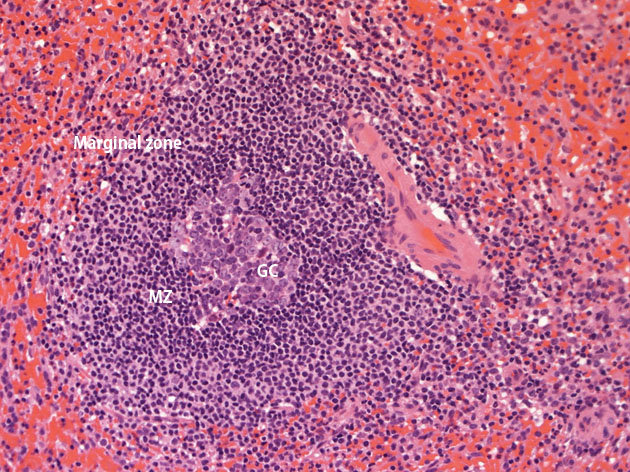

Spleen 白脾髄の組織像(二次濾胞). GC:germinal center, MZ:Mantle zone, Marginal zone.

白脾髄(white pulp)は毛細動脈を囲むように形成され, 赤脾髄との境をつくる辺縁部と動脈の間には主にT細胞により構成された動脈周囲リンパ球鞘(periarterial lymphoid sheath: PALS)とB細胞を中心とする一次濾胞が認められる.